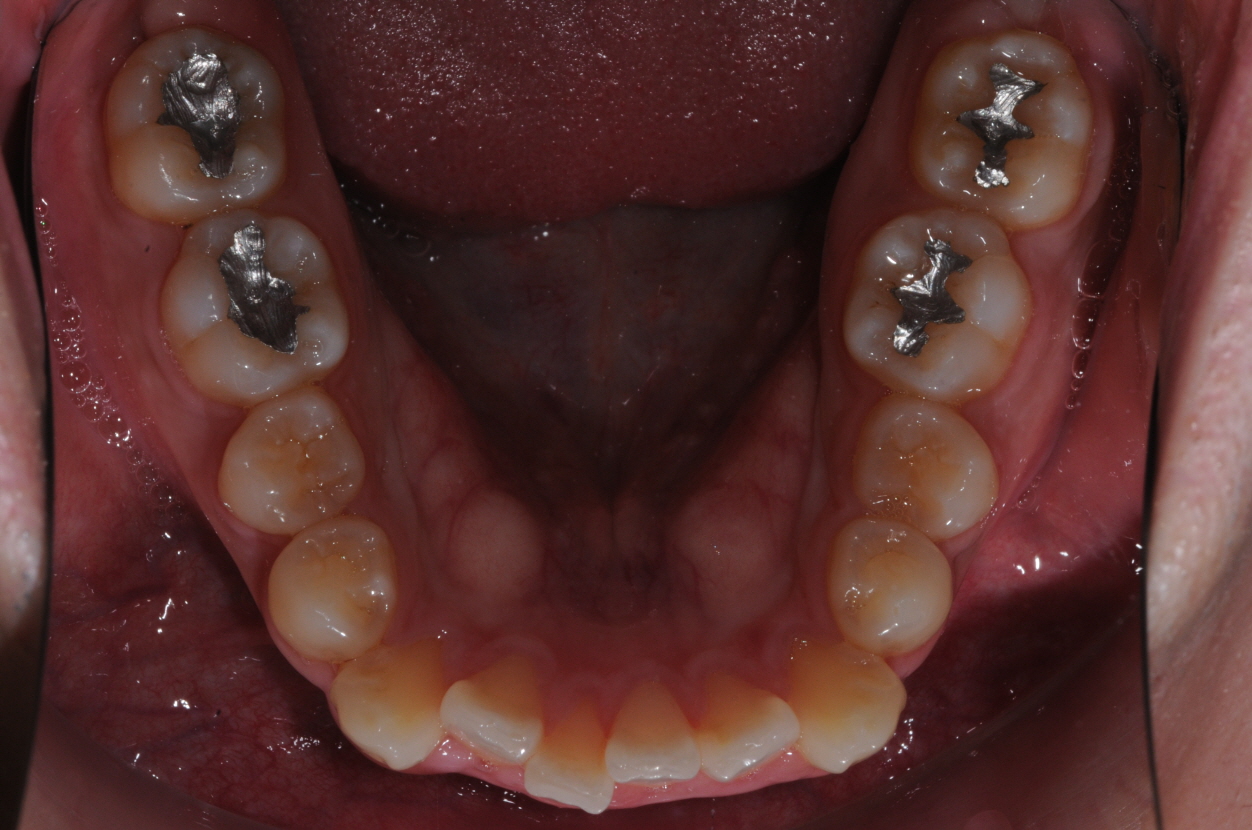

네... 사진 잘 보았습니다. 고민이 많이 되겠군요. 님의 상태는 일반적인 돌출입 부정교합이라고 판단이 됩니다. 그리 어려운 요소도 없구요. 일반적인 브라켓 교정치료로 진행하여도 1년반에서 2년 사이정도에서 교정이 이뤄지리라 예상이 됩니다. 님이 문의하신 교정법들은 치아의 이동을 좀더 빠르게 하는 조치들 인데요. 대략 6개월정도의 단축 효과정도 있으리라 생각이 됩니다. 즉, 1년 남짓정도는 걸리게 되지요. 1번과 3번의 치료방법은 수술의 심적인 부담이 많은 편이랍니다. 2번의 치료는 돌출된 입의 선행적인 치료가 장점이고 치료기간의 메리트는 그리 없지요. 저의 경우는 킬본 교정이라는 장치를 사용하여 2번의 방식데로 치료를 하는 경우가 많이 있는데 주 목적은 치료기간의 단축에 있는 것이 아니라 잇몸돌출의 해소와 앞서 언급한 돌출의 선행적인 해소에 있답니다. 4번의 방법은 님이 진동기를 일정시간 물고 있는 것인데 저는 사용을 하지 않아 뭐라 말씀을 드리기가 그렇습니다. 어쨋든 1번부터 4번까지의 치료는 특별한 부작용이 있는 치료들은 아니랍니다. 님이 언급한 교정치료 중의 애로사항인 심미적인 부분은 장치의 위치를 안으로하는 방법등을 고려해 볼 수 있구요. 발음은 교정치료 후 3개월 정도 되면 대부분 적응을 하는 것 같습니다. 참고가 되셨는지 모르겠네요...^^